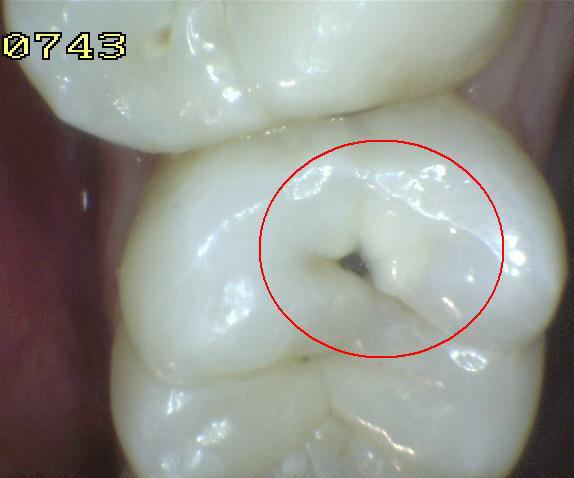

Código 3:

Ruptura localizada del esmalte debido a caries sin dentina visible

- El diente visto en estado

húmedo pueden tener una clara opacidad de caries (lesión de

mancha blanca)

y / o decoloración marrón de caries que es más ancha que la

fisura natural y la fosa, que no es consistente con la

apariencia clínica de esmalte sano. Una vez seco, se

observa una pérdida de estructura dental cariada en la

entrada, o dentro de la fosa o fisura . Esto se ve

visualmente como evidencia de desmineralización en la

entrada o dentro de la fisura o fosa, y aunque la fosa o

fisura puede aparecer sustancialmente más ancha que lo

natural, la dentina no es visible en las paredes o la base

de la cavidad ó discontinuidad .

En caso de duda, o

para confirmar la evaluación visual, la sonda de la OMS /

IPC / PSR puede ser

utilizada con cuidado a través de la superficie del diente,

para confirmar la presencia de una cavidad ( < 0,5mm.de

profundidad) al parecer limitada al esmalte . La

identificación de la cavidad se consigue deslizando el

extremo de la bola a lo largo de la fosa o fisura

sospechosa.